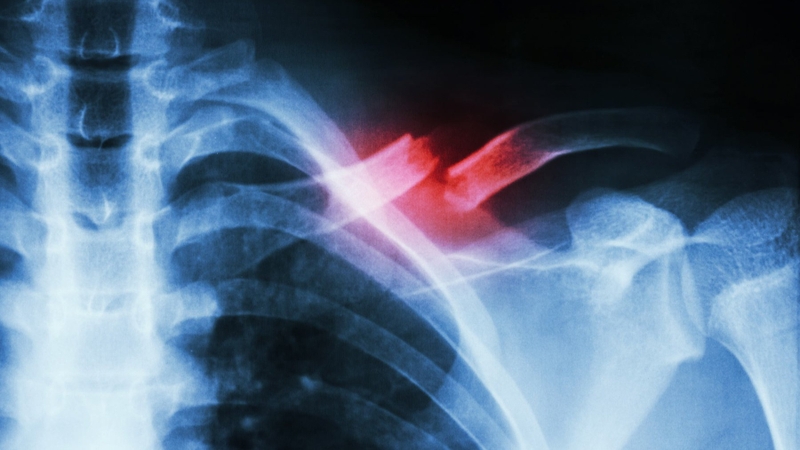

Xương đòn hay còn gọi là xương quai xanh, điểm nối xương ức và đai vai - cánh tay. Xương đòn có vai trò như thanh chống giữa thân mình và khớp bả vai, giúp vai hoạt động dễ dàng hơn. Nguyên nhân gãy xương đòn có thể là do chấn thương tai nạn giao thông hoặc tai nạn lao động. Gãy xương đòn thường gặp ở vùng vai với tỷ lệ người trẻ tuổi bị cao hơn so với người lớn tuổi. Thời gian hồi phục gãy xương đòn tùy thuộc vào mức độ nặng nhẹ. Ở mức độ nhẹ không cần phẫu thuật thì sau khoảng 4 - 6 tuần vết thương sẽ lành. Mức độ nặng hơn cần phẫu thuật thì thời gian lành vết thương có thể lên đến 3 tháng.